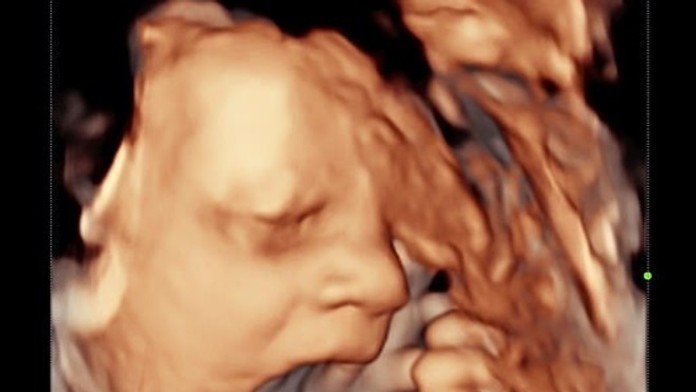

Pár počas predpôrodného ultrazvuku zostal v nemom úžase. Bábätko ukázalo šokujúce gesto

Neverili vlastným očiam. Pár z britského Cheshiru zostal v šoku po tom, aký pohľad sa im zjavil počas predpôrodného vyšetrenia. Píše Daily Mail.

Jesse Johnsonová (24) sa rozhodla, že si zaplatí súkromný takzvaný 4D ultrazvuk, aby jej snúbenec David Lewis mohol spolu s ňou vidieť svoje dieťa, nakoľko pre pandémiu koronavírusu nebolo možné navštíviť nemocnicu.

Budúci rodičia však zostali poriadne zaskočení. Na úsmevných snímkach rodičia mohli vidieť, ako si chlapček zakrýva tvár a následne sa zdá, že sa otočí smerom k rodičom a ukáže im vztýčený stredný prst.

Jess žartovala, že dieťa tým akoby chcelo naznačiť, že už má dosť skenovania. David dodal, že podľa tohto gesta mu je asi jasné, po kom bude.

„Je skvelé, že to videl aj môj partner, pretože si myslím, že by mi neveril, keby som mu o tom povedala," hovorí Jess.